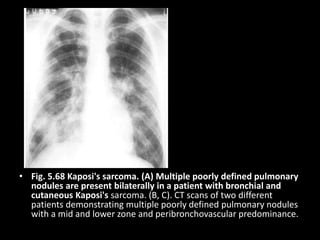

• Fig. 5.68 Kaposi's sarcoma. (A) Multiple poorly defined pulmonary

nodules are present bilaterally in a patient with bronchial and

cutaneous Kaposi's sarcoma. (B, C). CT scans of two different

patients demonstrating multiple poorly defined pulmonary nodules

with a mid and lower zone and peribronchovascular predominance.

• Fig. 5.68Kaposi's sarcoma. (A) Multiple poorly defined pulmonary nodules are present bilaterally in a patient with bronchial and cutaneous Kaposi's sarcoma. (B, C). CT scans of two different patients demonstrating multiple poorly defined pulmonary nodules with a mid and lower zone and peribronchovascular predominance.